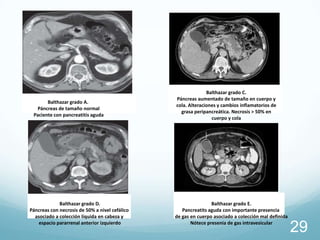

Balthazar grado A.

Páncreas de tamaño normal

Paciente con pancreatitis aguda

Balthazar grado D.

Páncreas con necrosis de 50% a nivel cefálico

asociado a colección líquida en cabeza y

espacio pararrenal anterior izquierdo

Balthazar grado C.

Páncreas aumentado de tamaño en cuerpo y

cola. Alteraciones y cambios inflamatorios de

grasa peripancreática. Necrosis > 50% en

cuerpo y cola

Balthazar grado E.

Pancreatits aguda con importante presencia

de gas en cuerpo asociado a colección mal definida

Nótece presenia de gas intravesicular